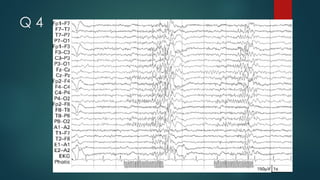

Q 4

A 4 photo paroxysmal response

The recording shows a burst of

generalized, polyspike wave discharges

occurring during and outlasting

photic stimulation,

defining a photo paroxysmal response.

The clinical and electrographic findings

are consistent with juvenile myoclonic

epilepsy